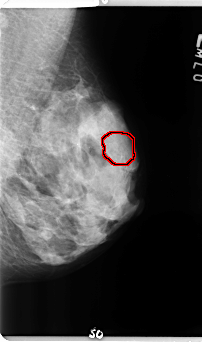

B_3358_1.LEFT_MLO

LEFT_MLO LINES 4784 PIXELS_PER_LINE 2816 BITS_PER_PIXEL 12 RESOLUTION 50 OVERLAY

FILE: B_3358_1.LEFT_MLO.OVERLAY

TOTAL_ABNORMALITIES 1

ABNORMALITY 1

LESION_TYPE CALCIFICATION TYPE ROUND_AND_REGULAR-PUNCTATE-AMORPHOUS DISTRIBUTION REGIONAL

ASSESSMENT 4

SUBTLETY 3

PATHOLOGY BENIGN

TOTAL_OUTLINES 1

BOUNDARY